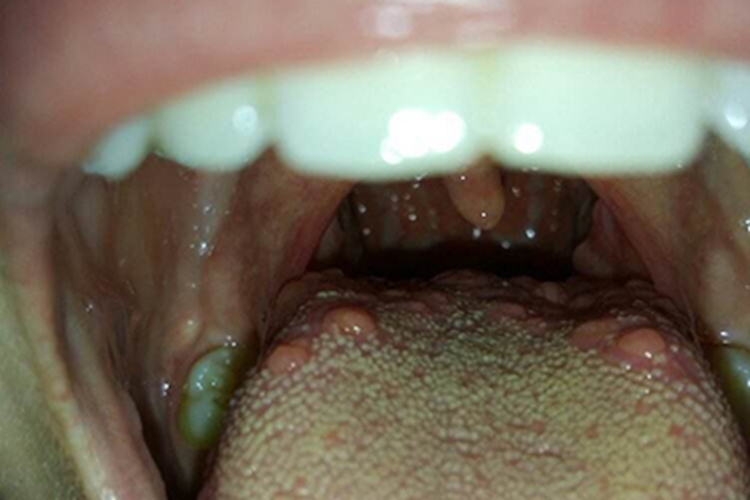

舌头后面有红色凸起肉粒,可能是舌乳头炎或舌癌,不同疾病的症状表现存在一定的差异,需要根据具体的情况进行分析判断。

舌乳头炎:可以在舌根部出现充血肿大的块状物,有刺痛、灼热感,进食时疼痛明显,严重时可能会影响言语功能。

舌癌:通常会发生于舌缘,其次是舌尖、舌背,常为溃疡型或外生菜花型、浸润型的舌部癌灶,可为红色、暗红色,同时患者会出现舌体运动的受限,以及颈部及颏下淋巴结肿大。